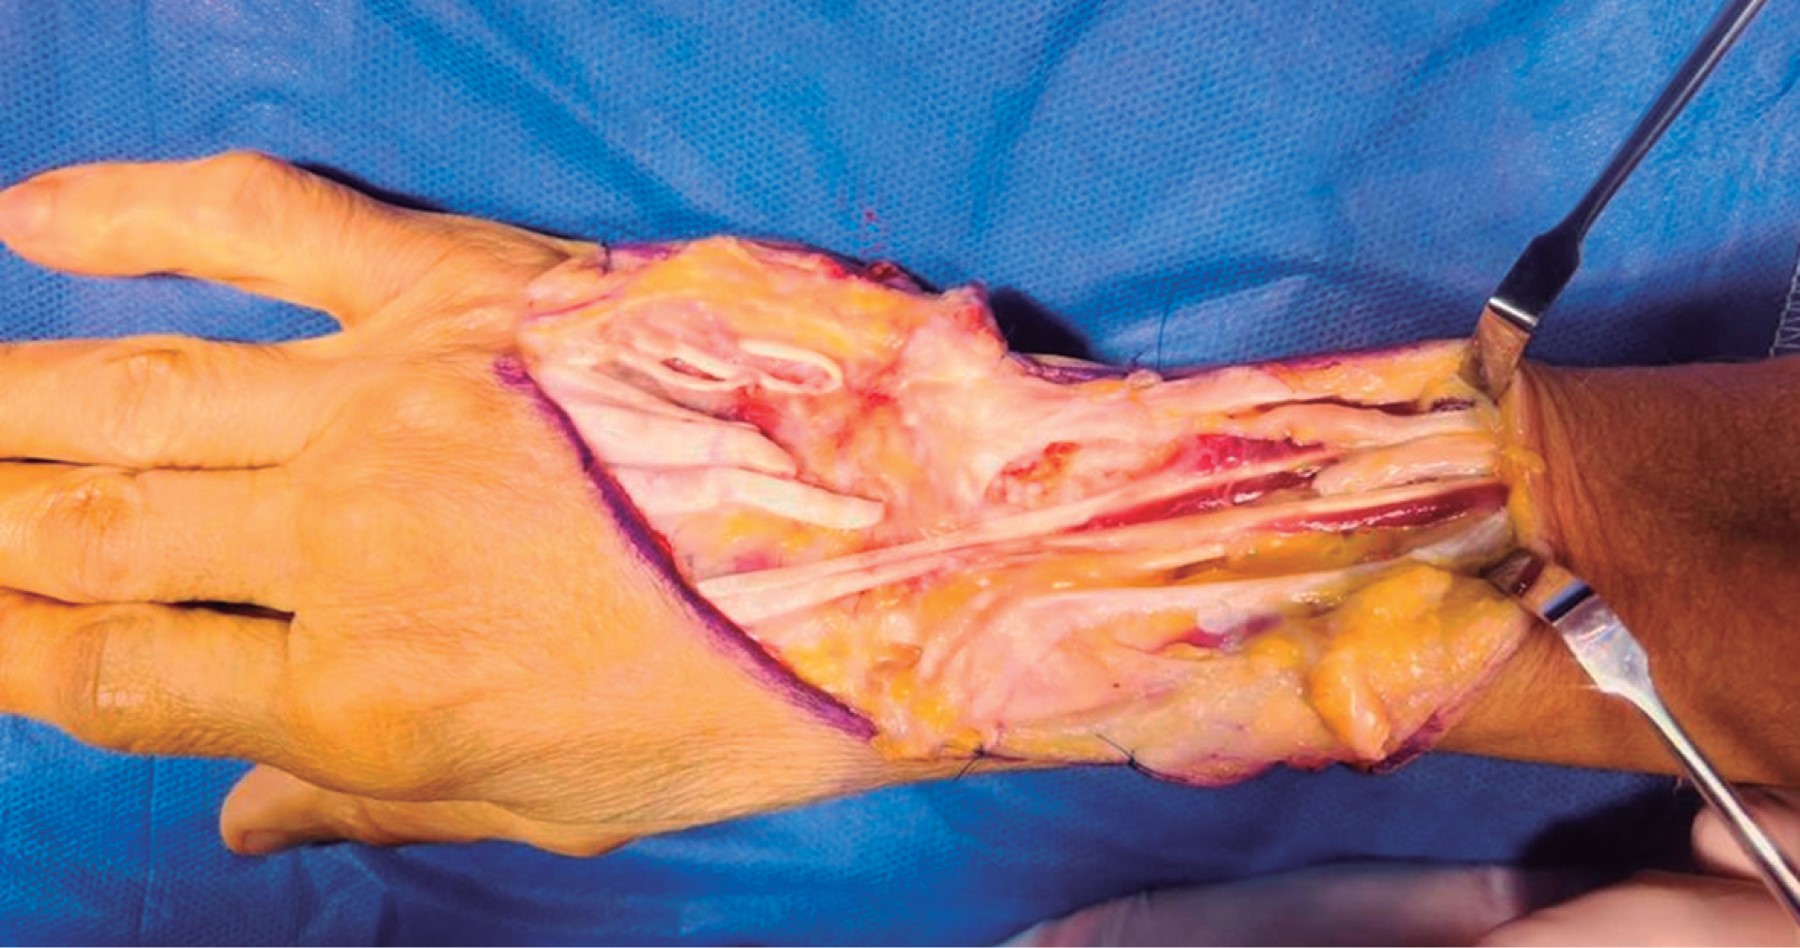

Se realizó exploración quirúrgica mediante incisión dorsal en forma de "S" itálica en zona V, VI y VII extensora. Se identificó el retináculo extensor y posteriormente se incidió longitudinalmente, realizando tenosinovectomía. Bajo visión directa se identificó sección total del tendón extensor común del tercer, cuarto y quinto dedos, así como del extensor propio del quinto dedo (Figura 3); los segmentos proximales de los tendones extensores comunes se mostraron con poca excursión y cambios de coloración a nivel del retináculo extensor. Como hallazgo se encontró ausencia del extensor carpi radialis brevis y longus y extensor cubital del carpo. El manejo quirúrgico consistió en realizar transferencia tendinosa del tendón extensor propio del segundo dedo al extensor común y propio del quinto dedo. Se realizó tenodesis término-laterales con técnica de Pulvertaft del tendón extensor común del cuarto dedo a tendón del propio de segundo dedo (Figuras 4 y 5). Después, se realizó resección de apófisis estiloides del cúbito y tenodesis término-laterales de segmentos proximales de tendones extensores a tendón extensor común de segundo dedo; lo anterior sin complicaciones trans o postquirúrgicas. Por último, se colocó inmovilización por un periodo de seis semanas con la muñeca en posición neutral, extensión a 0 grados de la articulación metacarpofalángica, dejando las interfalángicas libres.

Figura 3